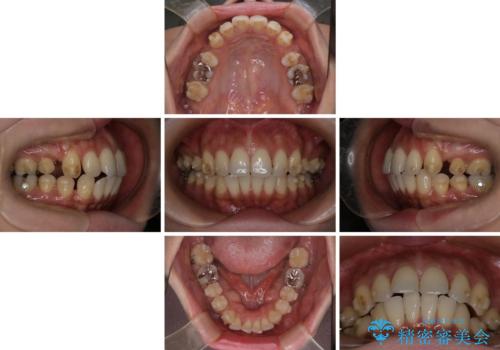

上顎前歯の突出を軽減 インビザラインによる抜歯矯正

- 上の前歯の突出感を気にして来院された患者様です。

目立たない装置を希望とのことで、上顎左右第一小臼歯を抜歯し、インビザラインにて矯正治療を行うこととしました。